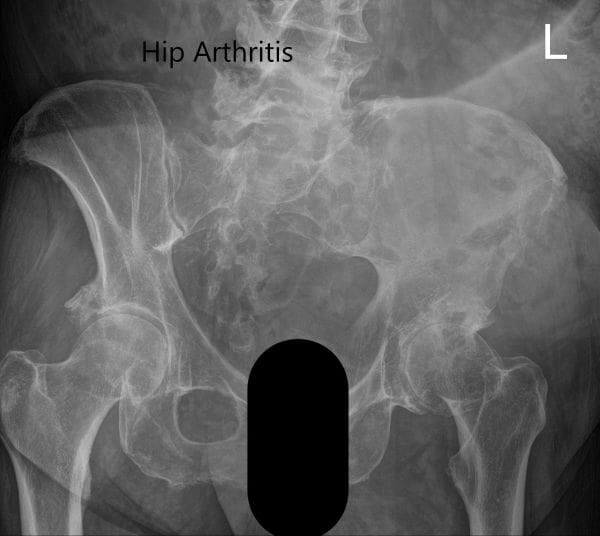

Las imágenes revelaron cambios osteoartríticos en la articulación izquierda de la cadera con reducción del espacio articular, quiste subcondral, esclerosis y osteófito. Tras agotar las opciones de manejo conservador, se recomendó al paciente una prótesis total de cadera. Se discutieron extensamente con el paciente los riesgos, beneficios y alternativas. Ella aceptó seguir adelante con el procedimiento.

Radiografía preoperatoria que muestra la vista Judet de la pelvis.

Radiografía preoperatoria que muestra la vista lateral en forma de rana y la vista en ángulo de la cadera izquierda.